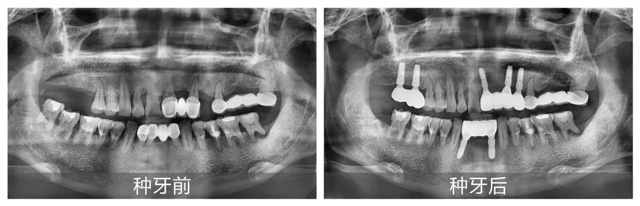

經CBCT全景檢查所見,謝海洋主任發現卞先生存在多顆牙缺失、殘存牙體伴有嚴重骨吸收,且多顆修復體失效等問題,亟待通過種植牙重建咬合功能。針對顧客異地就醫、就診時間有限的情況,謝海洋主任為卞先生制定了“上下頜多顆即拔即種+連冠修復”的個性化種植方案:下頜種植2顆基牙支撐2顆連冠,上頜右側種植2顆獨立基牙,上頜前側種植3顆基牙連冠修復1顆。